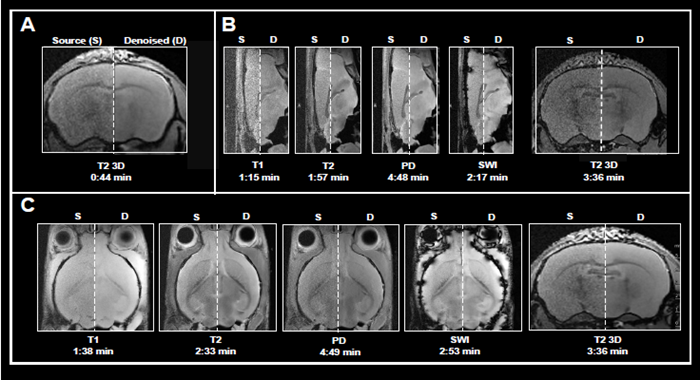

This article shows the application of Smart Noise Reduction to denoise rapid structural brain scans. Fig 4 depicts instances of ex vivo brain scans with various contrasts and orientations collected in less than five minutes. The data was collected from sensors operating at 3, 7, and 9.4 Tesla.

To accomplish the desired short acquisition time, conventional procedures produced for each system were modified to remove averaging (Fig 4A-C). This resulted in 7-15 faster acquisition times than the original protocols.

With the specified resolution, however, no averaging produced noisy images. Reconstructing the obtained data with the denoising algorithm effectively reduced noise from images and produced high-quality results.

Figure 4. Examples of fast brain scans. Ex vivo data of a fixed mouse head acquired with different image contrasts, geometries and orientations. Data were acquired at A) 3 Tesla, B) 7 Tesla, and C) 9.4 Tesla. Images were reconstructed with no denoising (Source) and with a network Strong and applying 50 % pre-denoising and a denoising level of 70 % (Denoised). Image Credit: Bruker BioSpin Group